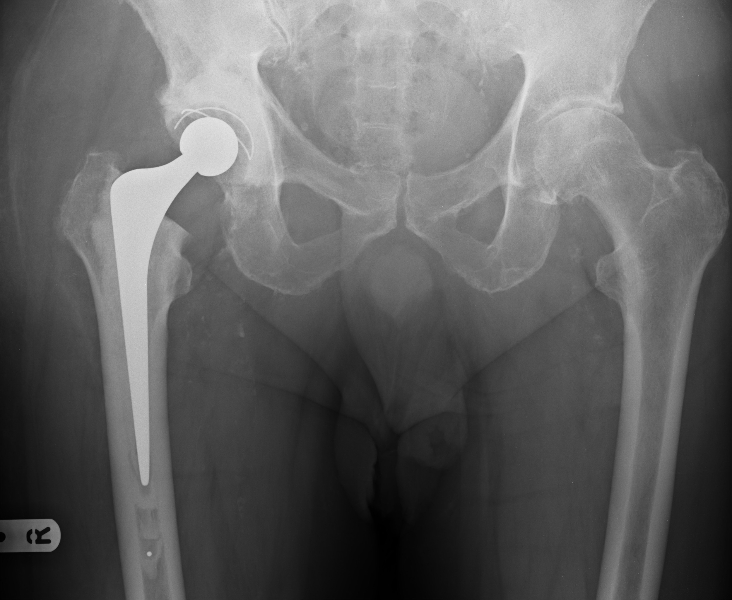

The spiky part in the marrow of my bone hurts like you would think. The top I also have mesh and other junk in me. That is what the scorpion twisted out of place.

Published August 19, 2015 in The Scorpion, Glasses and Osteonecrosis… | Full size is 732 × 600 pixels